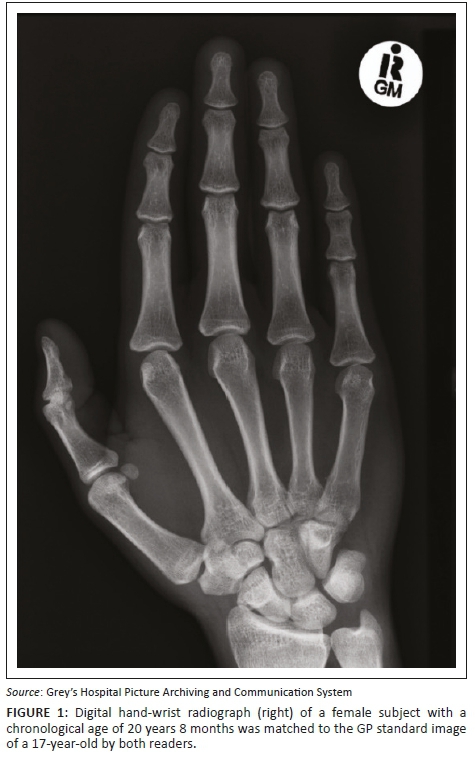

Digital hand-wrist images obtained by computed radiography were accessed from the Picture Archiving and Communication System (see Figures 1 and 2). Antero-posterior (AP) or postero-anterior (PA) views including the phalanges, metacarpals, carpals, distal ulna and radius were used. The GP atlas uses the left hand-wrist radiograph by convention as a standard for SA assessment. When images of both hands for the same patient were available, the left-sided radiograph was used. If only the right-sided radiograph was available, then this was used. All the radiographs included in the study were of outpatients who had been imaged in the emergency department for suspected trauma as identified by the history provided on the imaging request form. Radiographs performed as part of the work up of significant medical or systemic disorders were specifically excluded.

According to the GP atlas, skeletal maturity is reached at 18 years for women and at 19 years for men. Table 4 shows the number of female patients who had achieved full skeletal maturity in different age groups. There were two female patients in the study population with a CA of 18. Only one of these female patients was found to be both chronologically and skeletally 18 years old. The other chronologically 18-year-old was estimated to have a SA of 15. Interestingly, there were two female patients with a CA of 20, who were found to have SAs of 18 and 17. One female patient with a CA of 16 had a SA of 18 (i.e. had attained skeletal maturity). Similarly, one female patient with a CA of 17 had a SA of 18.